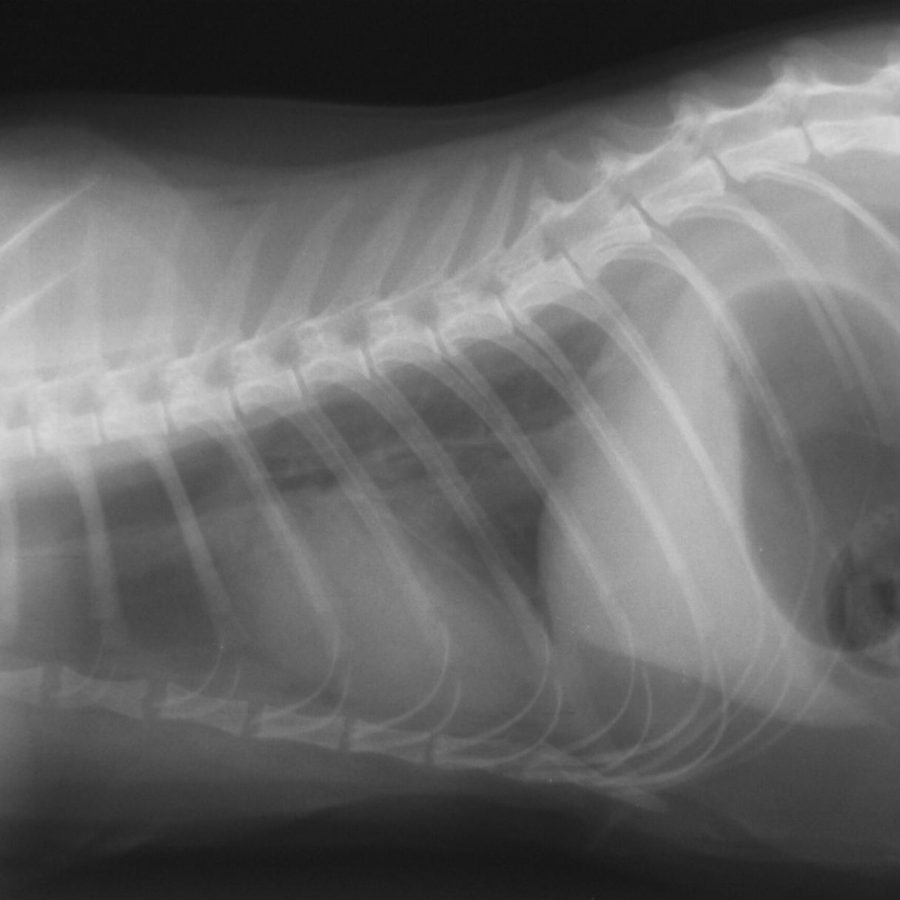

Правой боковой проекции

Правой боковой проекции 109 фото